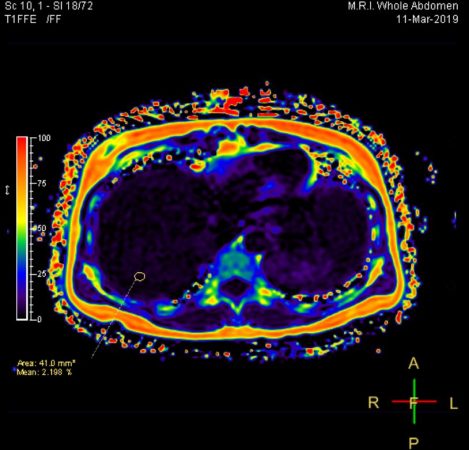

- การตรวจค่าการทำงานของตับ จากเอนไซม์ AST (SGOT) และ ALT (SGPT) ที่ร่างกายสร้างขึ้นเมื่อตับเกิดความเสียหาย เอนไซม์ Alkaline phosphatase (ALP), Gamma GT (GGT) และบิลิรูบิน (bilirubin) เพื่อดูความผิดปกติของตับและการอุดตันของท่อน้ำดี ร่วมกับการตรวจทางรังสีที่ตับและช่องท้อง ได้แก่ อัลตราซาวด์ช่องท้อง (Abdominal Ultrasound) โดยใช้คลื่นความถี่ และการตรวจด้วยเครื่องแม่เหล็กไฟฟ้า หรือการ MRI ช่องท้องความละเอียดสูงแบบไม่ฉีดสี (MRI Whole Abdomen Non-contrast) ช่วยในการประเมินความผิดปกติต่างๆ เช่น เปอร์เซ็นต์ไขมันพอกตับ, ภาวะไขมันพอกตับ (Fatty Liver) และภาวะไขมันพอกตับอ่อน (Fatty Pancreas), ก้อนเนื้อที่ผิดปกติ หรือเนื้องอกที่อาจพัฒนากลายเป็นมะเร็ง, ความผิดปกติที่ท่อน้ำดีและนิ่วในถุงน้ำดี, ฝีในตับ และการไหลเวียนของเส้นเลือดภายในช่องท้อง

การตรวจสุขภาพตับอย่างสม่ำเสมอ ช่วยให้สามารถวางแผนป้องกันไม่ให้ตับแข็ง และตับอ่อนแข็ง ซึ่งถือเป็นความเสียหายอย่างถาวรของเนื้อเยื่อตับ รวมถึงช่วยให้ค้นพบมะเร็งได้ตั้งแต่ระยะเริ่มต้น เพื่อให้เกิดการรักษาได้อย่างทันท่วงทีไม่ให้เกิดการแพร่กระจายของมะเร็ง